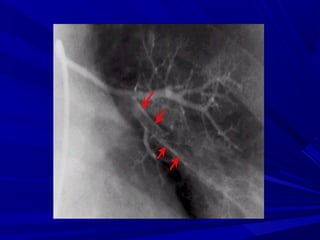

(3) Pulmonary angiography

• Some still consider it as the standard

technique for diagnosis of PE, but in reality

it is infrequently performed as it is:

• Expensive.

• Technically more difficult.

• Risky.

• Moreover there are limitations for

unequivocal diagnosis of isolated peripheral

pulmonary emboli.